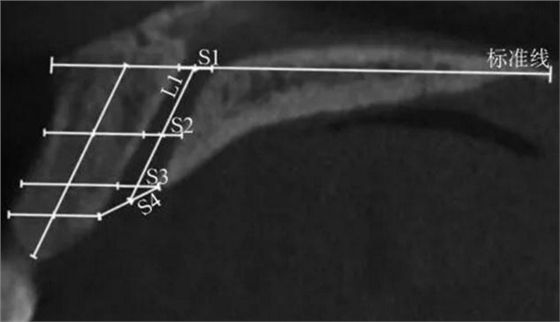

(1)正中矢狀面(圖1~3)。所使用的測量參數(shù)及其定義如下所述。鼻腭管高位直徑(S1):標準線交鼻腭管處的管徑;鼻腭管中位直徑(S2):鼻腭管長軸中點處的管徑;鼻腭管低位直徑(S3):管后壁腭側骨最低點至對應管前壁的水平管徑;切牙孔開口直徑(S4):管后壁腭側骨最低點至唇側骨低位厚度和管前壁交點的直線距離。唇側骨高位厚度(T1):S2平面處唇側骨板水平厚度;唇側骨中位厚度(T2):S3平面處唇側骨板水平厚度;唇側骨低位厚度(T3):唇側骨最凸處骨板水平厚度。鼻腭管長度(L1):S1與S4中點間的距離;唇側骨長度(L2):唇側骨下端最低點經(jīng)T1、T3中點至標準線的直線長度。鼻腭管傾斜角度(A1):L1和標準線的垂線所成角度;唇側骨傾斜角度(A2):L2和標準線的垂線所成角度。

S1:鼻腭管高位直徑;

S2:鼻腭管中位直徑;

S3:鼻腭管低位直徑;

S4:切牙孔開口直徑;L1:鼻腭管長度。

圖 1 矢狀面鼻腭管管徑測量方法

Fig 1 Measurements ofnasopalatine canal